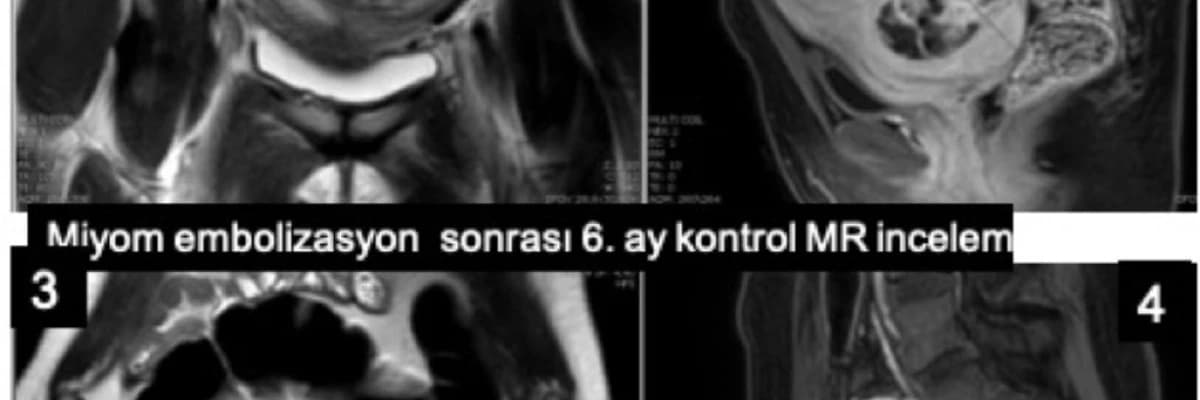

Miyom embolizasyondan sonra uygulanan miyomektomilerde de ameliyat sırasında kan kaybının çok azaldığı, ameliyatın çok daha kolaylaştığı ve rahimden daha fazla sayıda miyomun çıkarılabildiği gösterilmiştir.Miyomektomi geçiren hastanın miyom embolizasyonu öncesi kontrol MR incelemesinde halen çok sayıda miyom izlenmektedir. 1. Koronal MR inclemesi, 2. Sagital ilaçlı MR incelemesi. Miyom embolizasyonu sonrası miyomların canlılığını yitirdiği ve belirgin olarak küçüldüğü izlenmektedir. 3. Koronal MR incelemesi, 4. Sagital ilaçlı MR incelemesi. Bu aşamadan sonra hamilelik mümkün olabilmektedir.